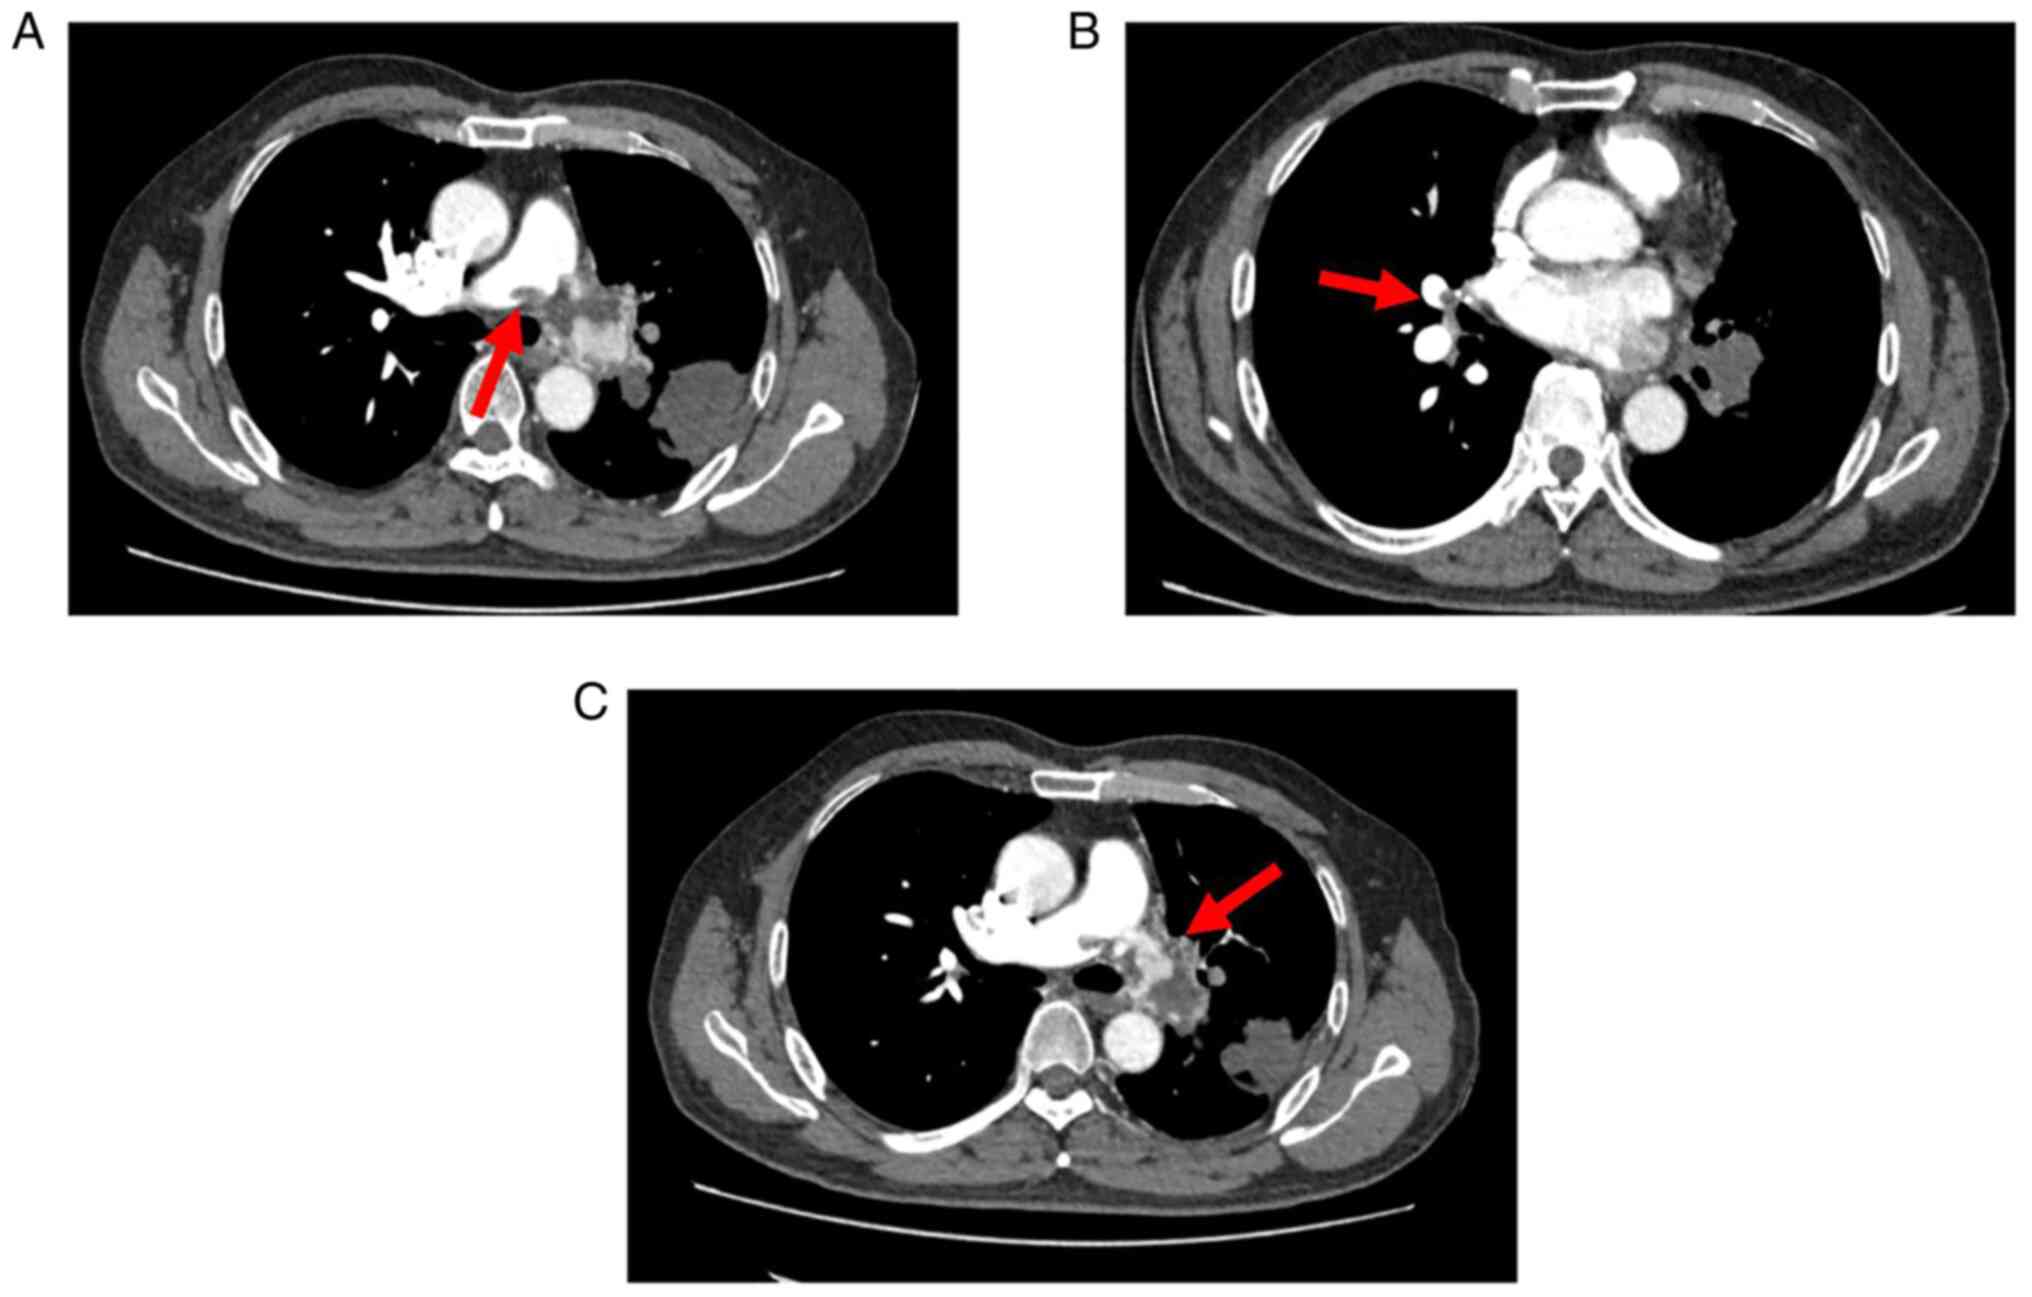

A 57-year-old male patient had complaints of dyspnea and wheezing following climbing 3 floors persisting for 6 months. Pulmonary artery computed tomography angiography (CTA) examination (Fig. 1) performed at an external hospital indicated that the left lower pulmonary artery and its branches had multiple pulmonary embolisms. The laboratory examinations included D-dimer (0.46 mg/l) and the tumor antigen markers carbohydrate antigen 19–9, carcinoembryonic antigen, α-fetoprotein and prostate-specific antigen (normal concentration values). The symptoms worsened following 3 months of irregular anticoagulation.

Figure 1.

Pulmonary artery CT angiography examination prior to anticoagulation treatment. (A) Left lower main pulmonary artery, (B) its proximal branch and (C) its distal branch were observed to have a large mural filling defect, which filled the lumen (red arrow). No filling defect was noted in the main trunk of the right pulmonary artery and its branches.